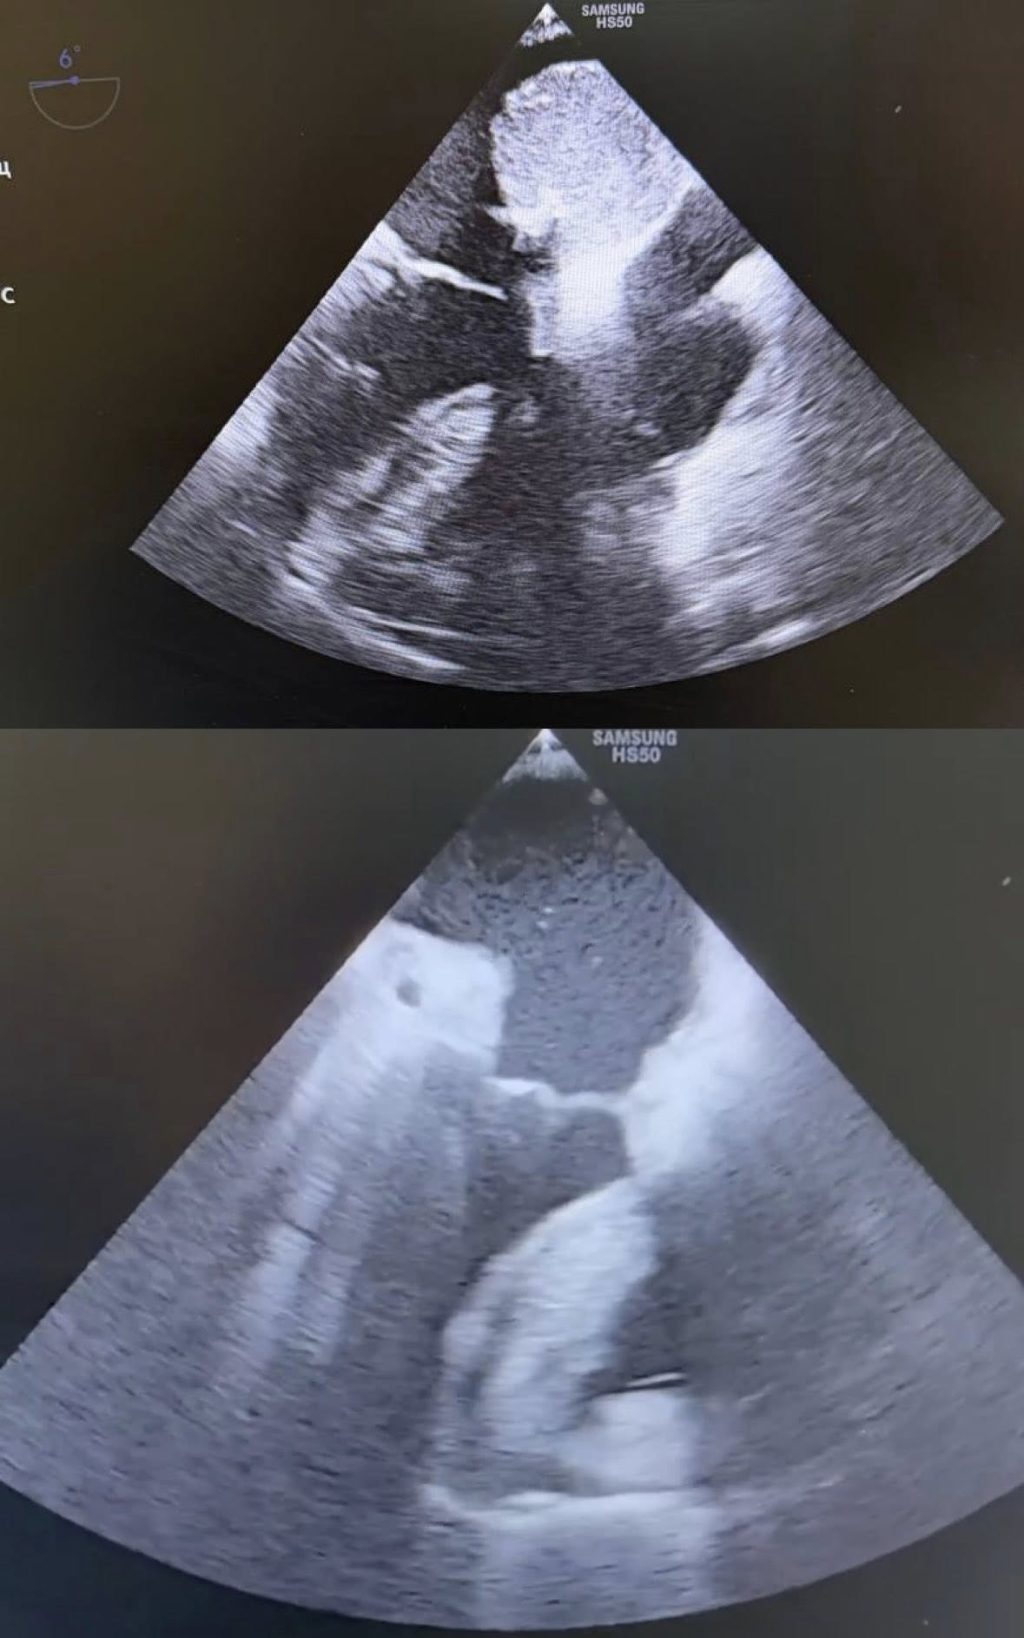

У лівому передсерді жінки медики виявили рухливу міксому серця — доброякісну, але вкрай небезпечну внутрішньосерцеву пухлину, що зміщувалася синхронно із серцевим циклом. Кожне скорочення серця відбувалося під ризиком перекриття клапанного отвору та системної емболії, що могло мати фатальні наслідки.

З огляду на високі ризики лікарі ухвалили рішення про невідкладне кардіохірургічне втручання. Операцію провели в умовах штучного кровообігу. Хірурги виконали атріотомію та радикально видалили пухлину, після чого відновили внутрішньосерцеву анатомію та стабілізували гемодинаміку.